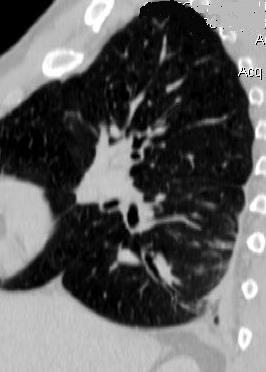

87. NEUMOTÓRAX ESPONTÁNEO

89. NEUMOTÓRAX. SÍNDROMES POROSOS

90. NEUMOTÓRAX A TENSIÓN

91. NEUMOTÓRAX EN ESPIRACIÓN

92. PLACAS PLEURALES

94. QUILOTÓRAX